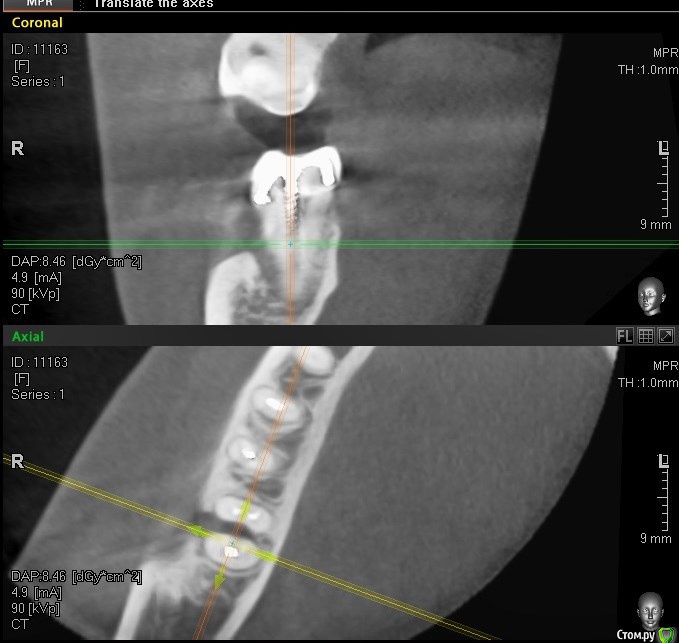

колесников Опубликовано 15 августа, 2016 Поделиться Опубликовано 15 августа, 2016 Здравствуйте, трещину седьмого зуба не увидел на кт, возможно в полости рта видно. На КТ он выглядит вполне нормально для попытки спасения.С шестым вот большой вопрос в сохранении, возможно нарушена целостность корня. Верхний шестой тоже обязательно лечить, вокруг корней тоже воспаление. Итого: то что видно на КТ. на трех зубах очаги воспаления. Трещин не видно ( их и не будет видно) Все три зуба можно попытаться вылечить, шансы 50/50. По моему всё очевидно. 37 трещина по бифуркации,тотальная резорбция межкорневой перегородки и ограниченно -вестибулярной пластинки. 36 перфорация медиального корня в верхней трети с очаговой деструкцией в области межкорневой перегородки. Итого: 37 удаляется без вариантов. 36 удаление можно отсрочить на несколько месяцев ,но шансы на восстановление у него призрачны (перспективы перелечивания с закрытием перфорации в устье канала сомнительны,плюс остаётся нерешаемый очаг деструкции в перегородке) 2 Ссылка на комментарий

DmitrySH Опубликовано 16 августа, 2016 Поделиться Опубликовано 16 августа, 2016 По моему всё очевидно. 37 трещина по бифуркации,тотальная резорбция межкорневой перегородки и ограниченно -вестибулярной пластинки. 36 перфорация медиального корня в верхней трети с очаговой деструкцией в области межкорневой перегородки. Итого: 37 удаляется без вариантов. Если это трещина, то очень странная. Коллега, все может быть, но по КТ( не самого лучшего качества) выносить приговор зубу.. я пас. 36 удаление можно отсрочить на несколько месяцев ,но шансы на восстановление у него призрачны (перспективы перелечивания с закрытием перфорации в устье канала сомнительны,плюс остаётся нерешаемый очаг деструкции в перегородке) Не хочу переводить тему во флуд, но опять все боятся процессов в фуркации. 1 Ссылка на комментарий

колесников Опубликовано 16 августа, 2016 Поделиться Опубликовано 16 августа, 2016 Не хочу переводить тему во флуд, но опять все боятся процессов в фуркации. Не все. Я ведь не сказал определённо да. Микроскоп,опыт,удача и зуб (36) ещё поработает. НО, где найти все 3 слагаемых? И главное стоит ли... Оставим на усмотрение лечащего врача пациентки. Ссылка на комментарий